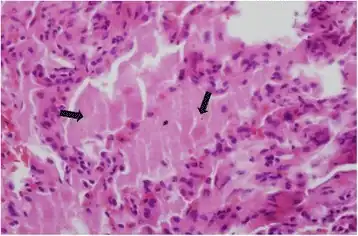

| Micrograph of pulmonary alveolar proteinosis, showing the characteristic airspace filling with focally dense globs referred to as chatter or dense bodies. H&E stain. | |

Lung washings or tissue for histopathologic analysis are most commonly obtained using bronchoalveolar lavage and/or lung biopsy.[12] Characteristic biopsy findings show filling of the alveoli (and sometimes terminal bronchioles) with an amorphous eosinophilic material, which stains strongly positive on PAS stain and the PAS diastase stain. The surrounding alveoli and pulmonary interstitium remain relatively normal.[13] Electron microscopy of the sample, although not typically performed due to impracticality, shows lamellated bodies representing surfactant.[14] An alternative diagnosis with similar histomorphologic findings is Pneumocystis jirovicii pneumonia.[14]

Lung washings characteristically yield a fluid which is "milky"composition. Under the microscope, samples show 20-50 micrometer PAS-positive globules on a background of finely granular or amorphous PAS-positive material. There is typically a low numbers of macrophages and inflammatory cells (although this is variable).[13][14]